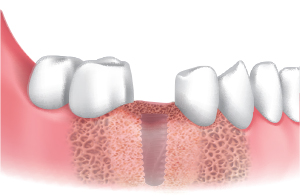

使用Ø3.5 / 4.0 / 4.5 / 5.0 / 6.0 Harvesting Drill采集颊骨。

根据直径和临床适应症。

在种植体植入部位周围移植采集好的骨片。